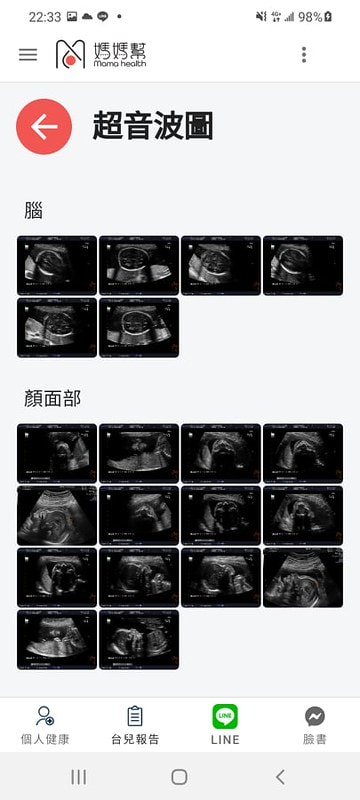

一般高層次超音波檢查會將逐一檢視以下項目:

1. 脊椎(頸椎、胸椎、腰椎、尾椎等)

2. 腦部(顱骨形狀、小腦、大腦側腦室、脈絡叢、透明中膈、後頸皮膚等)

3. 顏面部(眼距、上顎骨、上唇、兩耳、臉部側面輪廓等)

4. 胸部(肺臟、心臟四腔圖、心室出口、肺動脈分支、主動脈弓等)

5. 腹部(胃腸肝膽腎臟膀胱等臟器、橫膈膜、前腹壁、臍動脈數目)

6. 四肢(上臂、前臂、手掌、大腿、小腿及腳掌)

7. 外生殖器

8. 胎盤位置

9. 羊水量

10. 子宮頸長度

11. 彩色都卜勒超音波檢查臍動脈及子宮動脈血流

產檢和各項檢查都能透過他們的app直接下載照片

超音波的照片跟報告結果

在上面直接看得到唷

照得非常詳細~

小萊姆的高層次超音波照完之後

除了左心室有小白點之外

基本上其他都可以說是正常

但其實醫生說小白點也很常見

讓我不用太擔心!